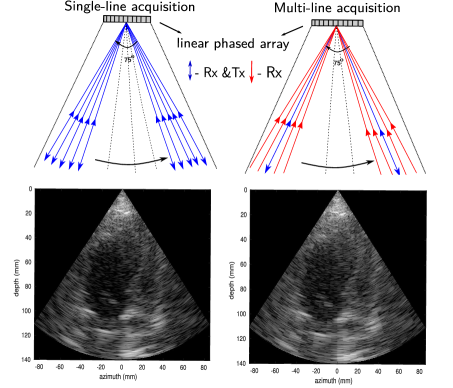

In an attempt to overcome the frame rate problem, the MLA method was proposed in [1], [3]. The main idea behind MLA is to transmit a weakly focused beam that provides a sufficiently wide coverage for a high number of received lines. On the receiver side, lines is constructed from the data acquired from each transmit event, thereby increasing the frame rate by (the latter number is usually referred to as the MLA factor). Signal formation in the SLA and MLA modalities is demonstrated in Figure 1 where -MLA is depicted. For a -MLA, we construct Rx lines per each Tx thus increasing the frame rate by the factor of .

As the Tx and Rx are no longer aligned in the MLA mode, the two-way beam profile is shifted towards the original transmit direction, making the lateral sampling irregular [2]. This beam warping effect causes sharp lateral discontinuities that are manifested as block artifacts in the image domain.

The observed block artifacts in the ultrasound images (see, e.g., Figure 1) tend to be more obvious when the number of transmit events decreases. The MLA artifact can be measured by assessing the correlation coefficient between each two adjacent Rx lines in the in-phase and quadrature (I/Q) demodulated beamformed data [4]. In SLA or compensated MLA, the averaged correlation values inside MLA groups and between MLA groups are almost the same. In the uncompensated cases, however, the correlation values are different.